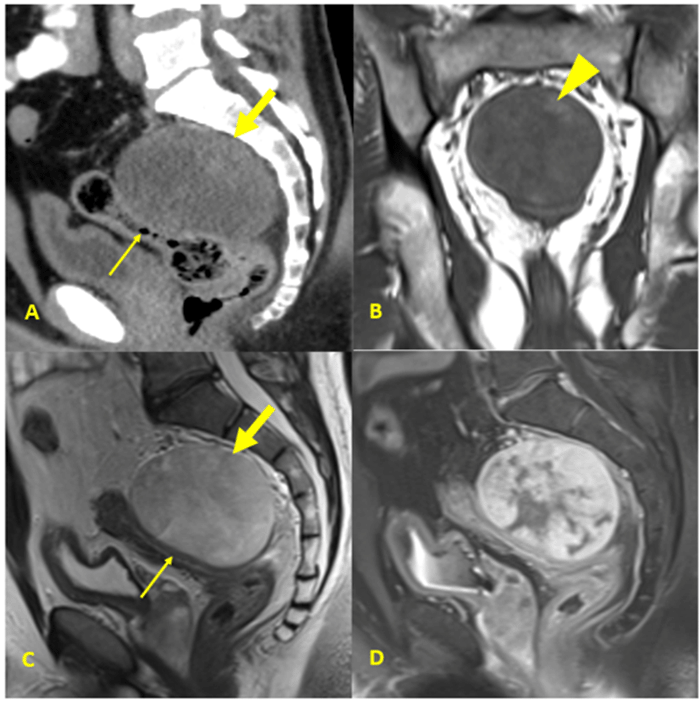

Although initial surveillance imaging was negative, pelvic MRI at one-year follow-up revealed interval development of a 9 cm well-circumscribed, heterogeneous retrorectal mass without regional lymphadenopathy (Figure 1). Staging CT of the chest, abdomen, pelvis did not show any other sites of disease. At this time, the patient was referred to us. Metastatic MLS was highly suspected given his history and subtle fat components in the tumor seen on a careful review of the imaging. The patient was treated with three cycles of trabectedin 1.5 mg/m2 intravenously every three weeks. Upon completion, restaging showed overall stable disease for the retrorectal tumor and, again, no other metastase.

Figure 1. Cross-sectional Images of Retrorectal Mass. Published with Permission

A) Sagittal reformat CT image shows retrorectal mass (thick arrow) with broad area of contact with rectum (thin arrow); B) coronal T1 MRI image shows isointense mesorectal mass. Focal areas of T1 hyperintense signal in mass are consistent with fat (arrowhead); C) sagittal T2 MRI image shows heterogeneously hyperintense mass (thick arrow) relative to muscle. Mass abuts rectum (thin arrow) without gross invasion; D) sagittal post-contrast T1 with fat saturation MRI image shows heterogeneous enhancement of mass